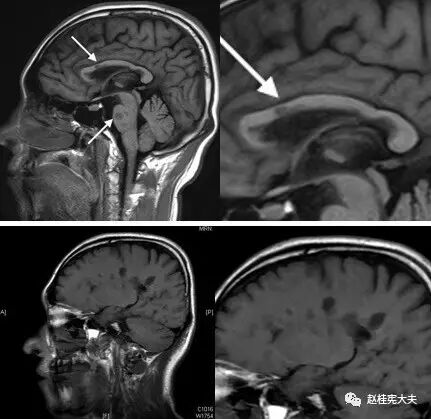

图4. 示T1矢状位像,胼胝体上缘可见多发斑片状低信号,“Dawnsing finger“即“指压征”。

图5. 示双侧放射冠区、侧脑室旁多发圆形、卵圆形或斑片状病灶,T2高信号,部分呈煎蛋征(双娇煎蛋)。(左侧侧脑室旁)病灶长轴与侧脑室长轴垂直。

图6. T2FLAIR薄层示双侧侧脑室旁、胼胝体多发斑片状高信号灶。

图7. 矢状位T1像示:胼胝体深部、侧脑室上缘,脑桥见多发斑片状低信号。